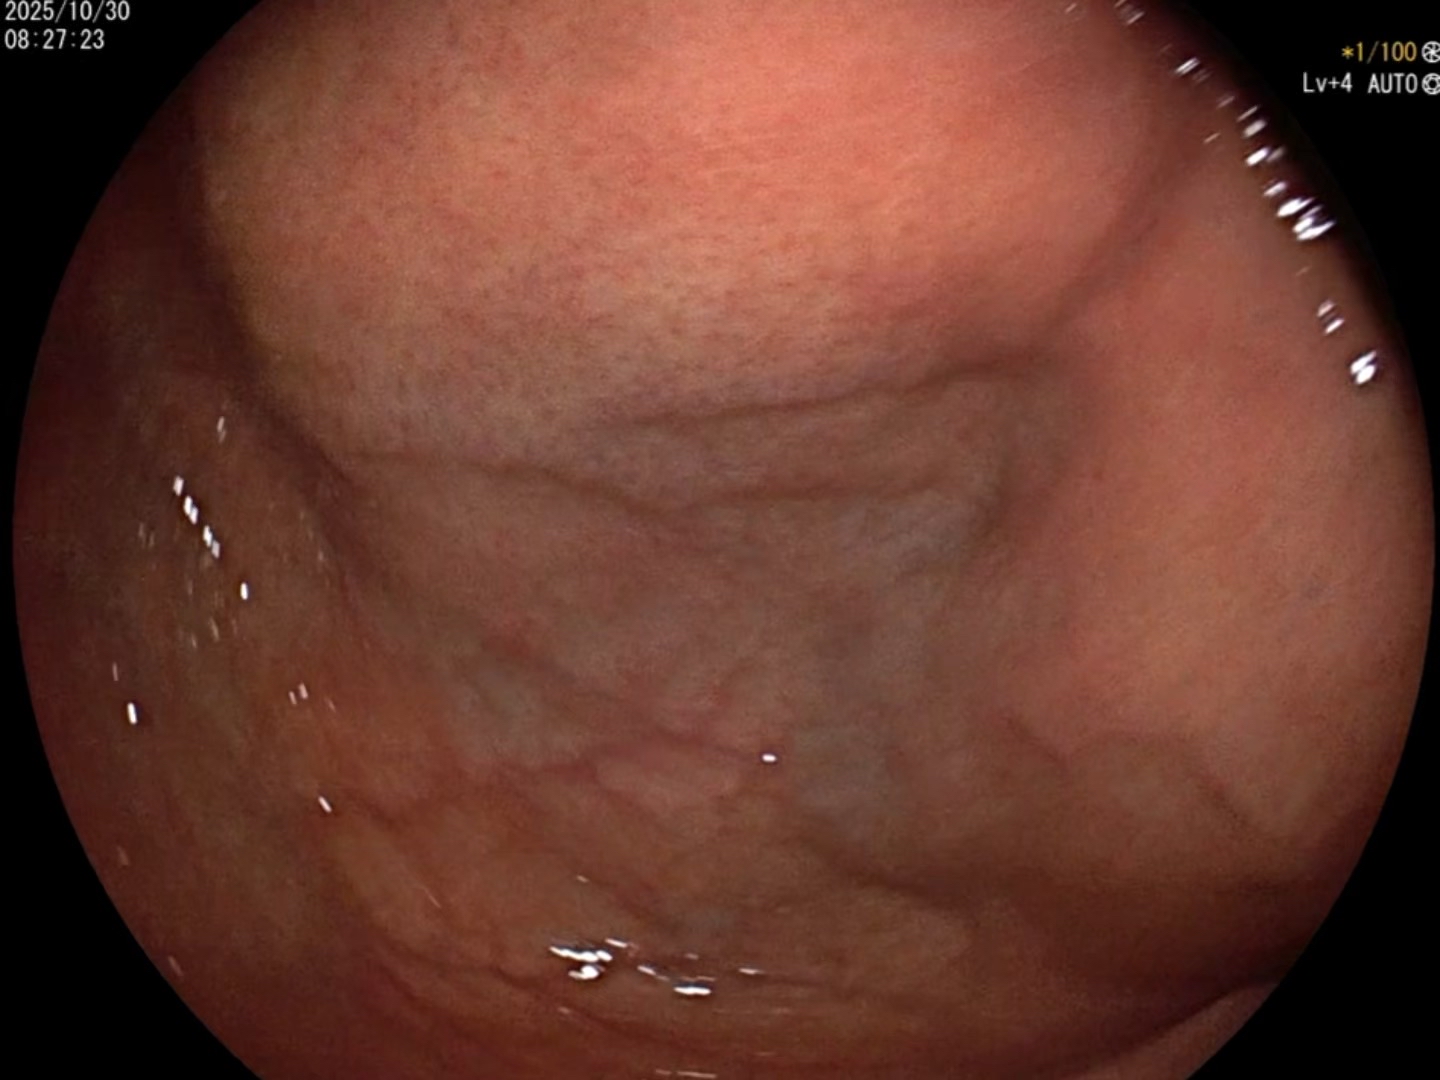

胃镜所见:胃底黏膜下微小隆起,表面见血管扩张。

胃底见约1.5mm褪色黏膜病变,边界可见,表面见血管扩张。